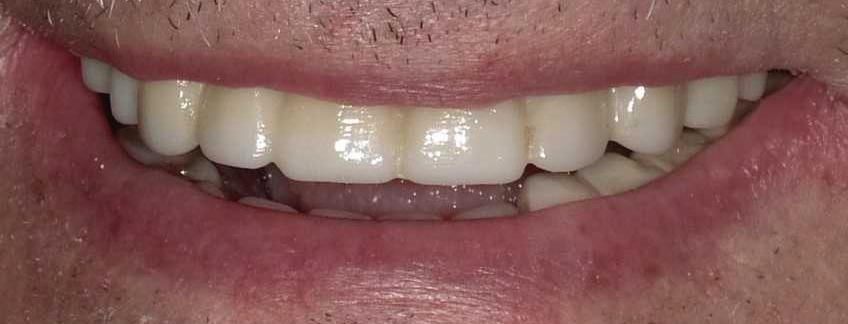

All-On-4 Dental Implants: A Reason To Smile Again

All-on-Four: One Full Arch Of Teeth, Four Dental Implants

To fully understand this remarkable technique for replacing teeth, you should first understand what a dental implant is. An implant is a small titanium screw that fits inside your jawbone and replaces the root-part of a missing tooth. Minor surgery is required to insert the implants. Once the implant is in place, a crown is attached to give you a highly realistic-looking and functional prosthetic tooth.

Here’s where it gets really interesting: You do not need a dental implant for each and every one of your missing teeth. All you need is four precisely placed implants on the top of your mouth, and four on the bottom, to restore your full smile. That’s the beauty of the all-on-four. And because the implant is made of titanium, it has the unique ability to fuse to living bone and function as part of it. So eventually, the dental implant becomes part of the jawbone and serves as a strong, long-lasting foundation for your new teeth.

Besides ensuring that your implants are permanently fixed in place, this bone fusion has another important benefit: it prevents future bone loss in the jaw. This helps to maintain a more youthful facial structure – and better oral health. But perhaps the biggest surprise about the all-on-four is how quickly it can transform your life.